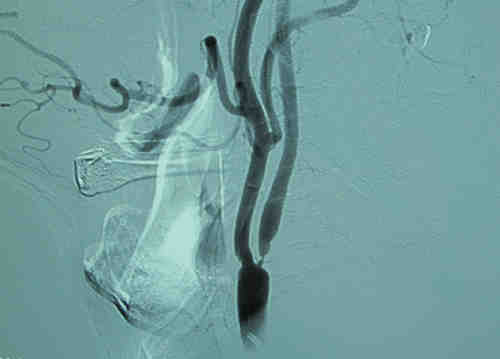

入院后行DSA 检查,见右侧颈内动脉起始段重度狭窄。

经完善各项术前准备,2012年8月8日,张勤奕教授受邀于北京大学人民医院行右侧颈动脉内膜剥脱术,手术圆满成功,患者恢复良好。